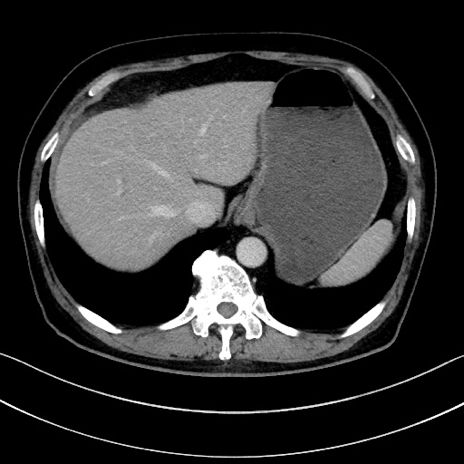

症例15(横断像)

【症例】70歳代男性

【主訴】腹痛

【現病歴】今朝から腹痛あり。全体的に痛い。特に左上の方。排ガスが今日はない。冷や汗が出る。

【既往歴】直腸癌術後

【身体所見】左側腹部〜上腹部に圧痛あり。腹膜刺激症状明らかなではない。軽度反跳痛。左下腹部に術後瘢痕あり。

【データ】WBC 7700、CRP 0.02